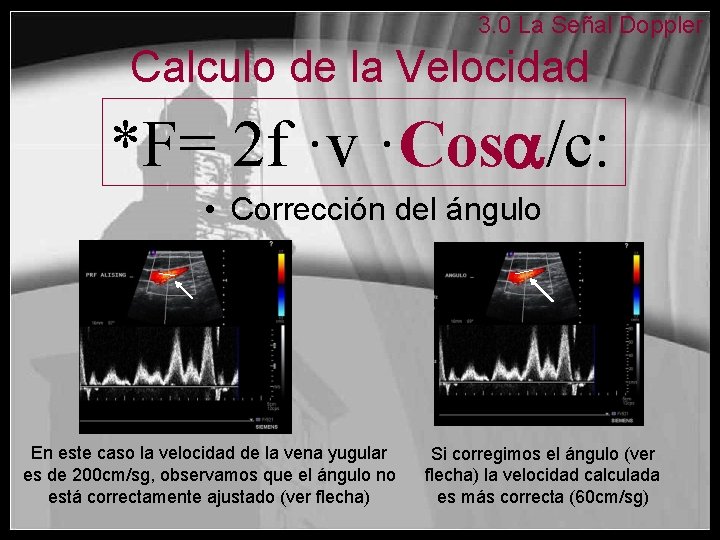

3. 0 La Señal Doppler Velocidad de flujo: Corrección del ángulo • La señal Doppler depende de la diferencia de frecuencias • Para calcular la velocidad del flujo debemos indicar el ángulo del vaso al procesador del ecógrafo para que aplique correctamente la fórmula del Doppler

3. 0 La Señal Doppler Calculo de la Velocidad *F= 2 f ·v ·Cos /c: • Corrección del ángulo En este caso la velocidad de la vena yugular es de 200 cm/sg, observamos que el ángulo no está correctamente ajustado (ver flecha) Si corregimos el ángulo (ver flecha) la velocidad calculada es más correcta (60 cm/sg)